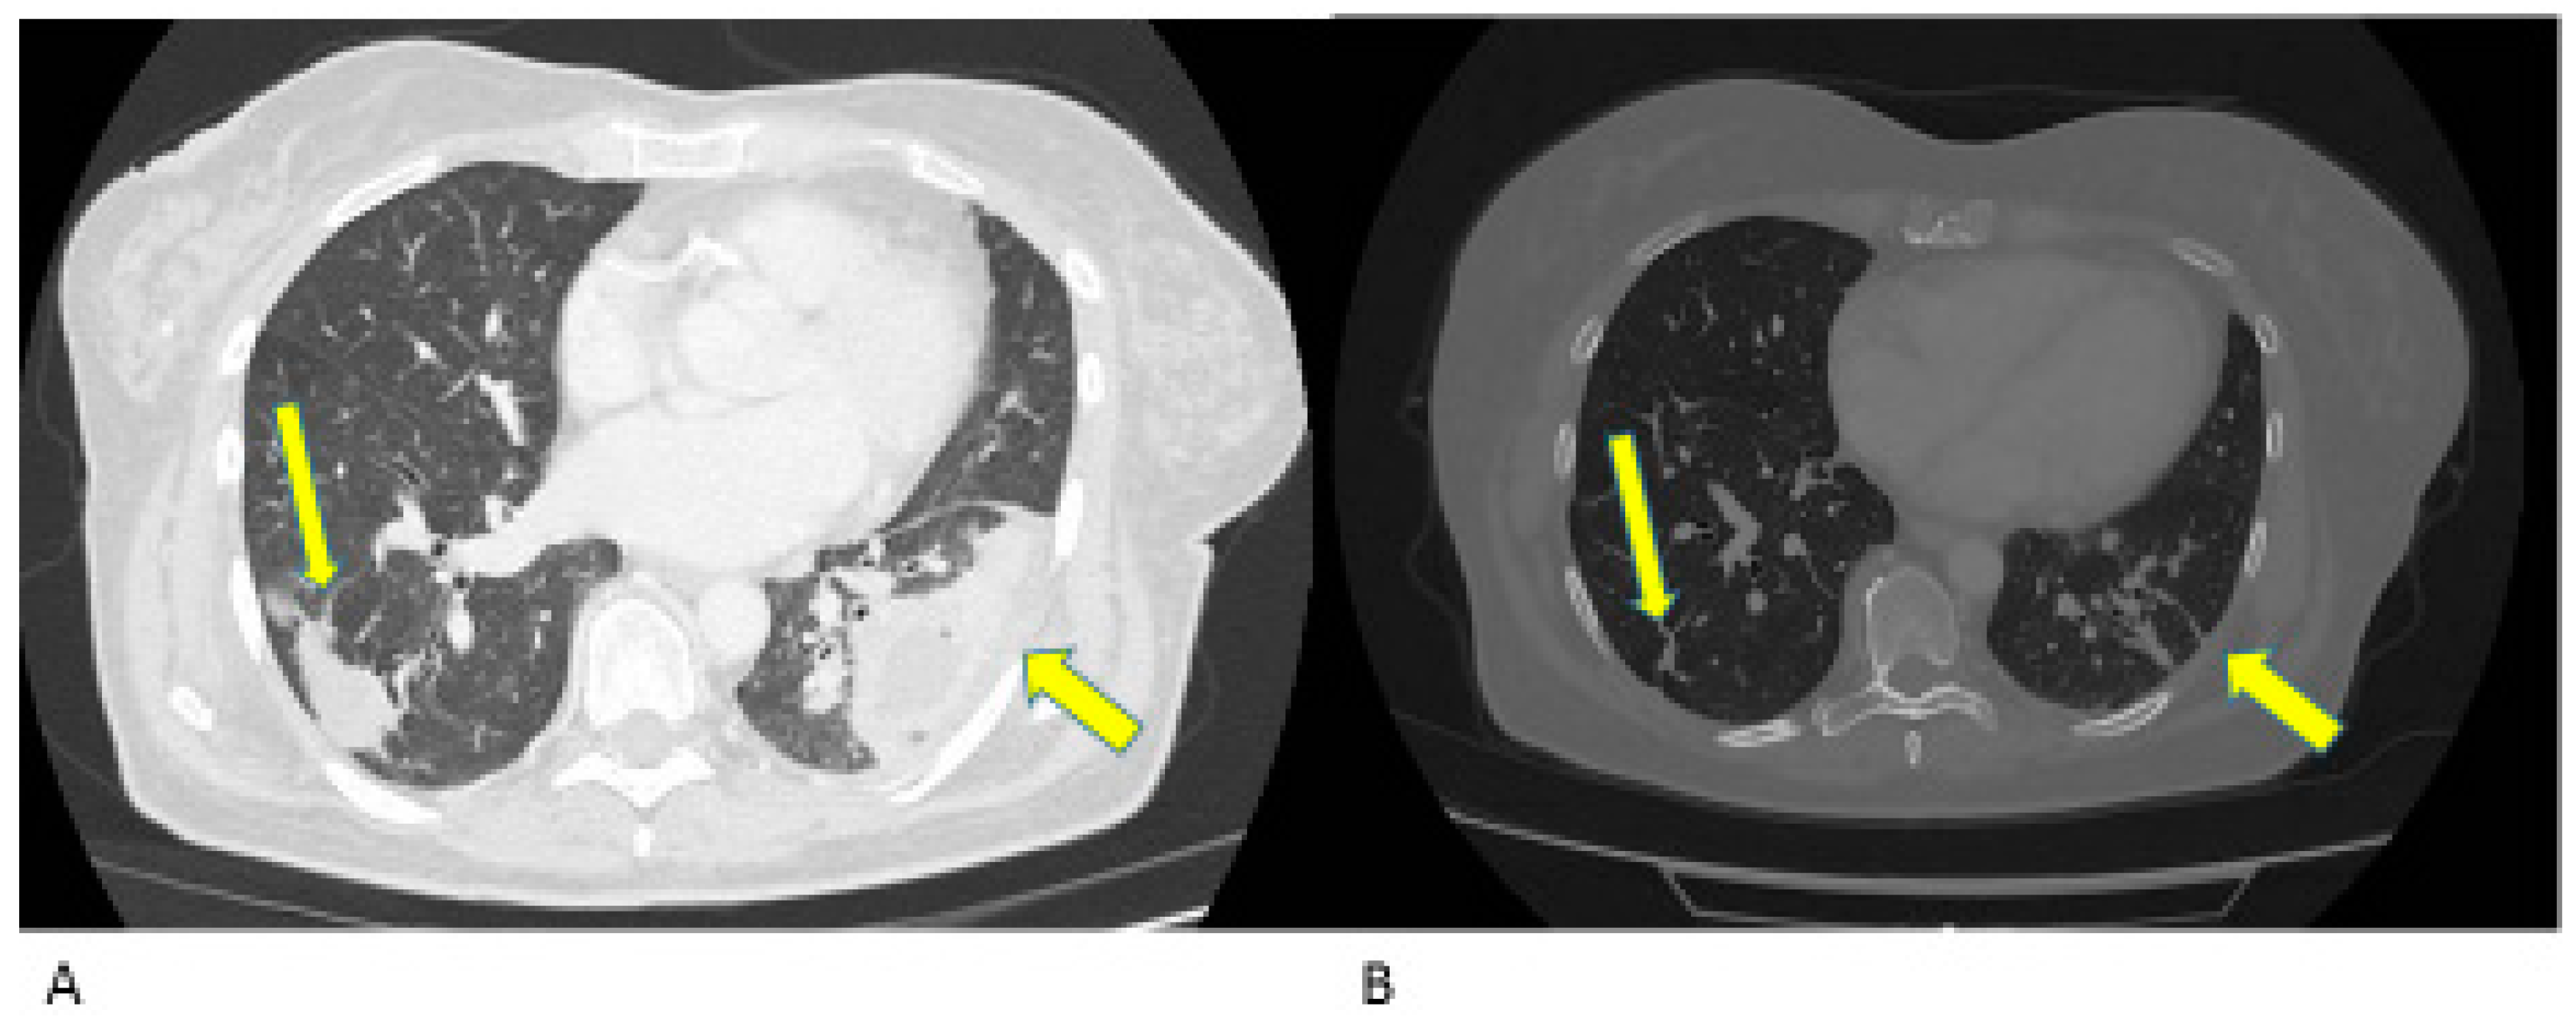

- Case 1:

- Case 2:

- Case 3:

- Case 4:

- Case 5:

- Case 6: